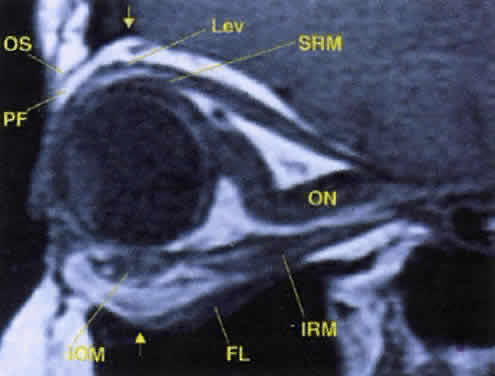

Veins Within the soft tissue of the orbit, venous drainage is distinctly separate from the arterial supply; a similar arrangement is found intracranially. Although the veins are found in a relatively reproducible pattern within the orbital septal system, the arteries travel more haphazardly within orbital fat.18 All orbital veins are valveless; this may facilitate more rapid posterior spread of infectious processes within the anterior orbit. The major venous drainage of the orbit is the superior ophthalmic vein and the CS (Fig. 21). The superior ophthalmic vein follows a medial-to-lateral route posteriorly along the superior orbit, tethered beneath the superior rectus muscle by a fascial sling.19 At the orbital apex, it is usually joined by the inferior ophthalmic vein, which also communicates through more minor branches with the pterygopalatine plexus through the IOF. The central retinal vein typically drains directly into the CS without joining the superior ophthalmic vein. Anteriorly, the orbit also drains into the angular vein of the facial plexus. Lymphatics To date, no lymphatic system has been identified within the human orbit, although recent studies that identified lymphatic drainage in primate orbits make this an intriguing possibility.20 In the eyelids, lymphatic drainage occurs through a deep (posterior lamellar) and superficial (anterior lamellar) system. The medial aspect of the eyelids drains into the submandibular lymph nodes, whereas the lateral aspect and most of the upper eyelid drain into the preauricular and parotid nodes. EXTRAOCULAR MUSCLES AND ORBITAL FASCIAL SYSTEM The EOMs insert 5.5 to 8 mm behind the limbus of the globe. Specific details regarding the dimensions and functions of each EOM are found elsewhere. Useful points are summarized in Table 6. The EOMs are striated and composed of aerobic, twitch-type Fibrillenstruktur fibers and anaerobic, tonic-type Felderstruktur fibers.36,37 The most common affliction of the EOMs is inflammatory myositis, which is seen most typically in thyroid-related orbitopathy and idiopathic inflammatory pseudotumor. Rhabdomyosarcoma, a tumor with focal striated muscle differentiation that generally occurs in children, appears to arise from indifferent orbital mesenchyme rather than from preformed and completely differentiated striated muscle fibers. Landmark anatomic investigations by Koornneef38–40 have shown that there are highly elaborate and reproducible connections of the epimysium of the EOMs with the fibrous connective tissue system of the orbital fat, the epibulbar fascia of Tenon's capsule, and the periosteum (periorbita) (Fig. 22). This extensive yet reproducible network of connective tissue provides support for the delicate neurovascular structures traversing the orbit, both facilitates and restricts the movement of EOMs in a coordinated fashion, and compartmentalizes the orbit into various spaces. Because of the inherent complexity of the orbital connective tissue system, any disruption in one area of the orbit may cause significant dysfunction of more distant areas. For example, these connections become clinically important in the understanding of restricted motility after orbital wall fracture and orbital decompressions for Graves' orbitopathy, as well as the superior sulcus and lower eyelid deformities that follow enucleation and orbital implant placement. To promote a clearer understanding, Dutton has succinctly summarized the orbital connective tissue system by dividing it into three components: Tenon's capsule, the anterior orbital suspensory system, and the posterior orbital suspensory system.41 The three components should not be considered as distinct anatomic entities, because complex attachments unite this triad into one comprehensive unit. Tenon's capsule begins anteriorly just posterior to the limbus with firm attachments to the underlying episclera, investing the globe in an elastic and vascular connective tissue cover. The capsule also encompasses the anterior portions of the EOMs. Posteriorly, Tenon's capsule surrounds the optic nerve, interdigitating with the dural sheath. Other than its anterior and posterior attachments to the globe, Tenon's capsule is only loosely adherent to the underlying sclera, thereby cushioning the movement of the globe. An intermuscular fibrous membrane connects the four rectus muscles around the globe to create a distinct intraconal space, but in the deeper orbital tissues this membranous system is not complete, so that the distinction between a central and a peripheral orbital space is lost toward the orbital apex. Anteriorly, the intermuscular fibers also blend with Tenon's capsule, creating a sort of rotating sleeve around the globe during ocular rotations. The anterior orbital suspensory system is primarily concerned with providing support for the globe and fixation for eyelid structures. In addition, fascial support exists for the lacrimal gland (Sommering's ligaments) and the superior oblique muscle in the area of the trochlea. The four main structures of the anterior system are Whitnall's suspensory ligament, Lockwood's ligament, and the medial and lateral canthal tendons. These structures are discussed in detail elsewhere. The anterior suspensory system also provides anchoring points for the check ligaments of the EOMs, limiting their overaction during ocular rotations. As already noted, the orbital septal system becomes less defined more posteriorly. The well-defined intraconal space encountered anteriorly blends with the surrounding extraconal space as one approaches the orbital apex. The annulus of Zinn, discussed earlier, forms dense adhesions to the periosteum of the orbital apex around the optic canal and SOF (see Fig. 12). In addition, fibers pass inferiorly along the IOF to interdigitate with Müller's orbital muscle, which spans the fissure. As the levator palpebrae superioris (levator) muscle and superior rectus muscle course anteriorly, diffuse connections form to the orbital roof, creating an effective suspensory system. Further, diffuse fascial connections form between the levator and superior rectus muscles, allowing precise coordination of upper eyelid retraction with upgaze. Note that on imaging studies, the close association of these two muscles often makes them look like a single anatomic unit; the term “levator-superior rectus complex”is often found in radiologic reports (see Fig. 17). A fascial sling forms beneath the superior rectus muscle to provide suspensory support for the superior ophthalmic vein. The medial rectus muscle has few important attachments to the posterior medial orbital wall, in contrast to the lateral rectus muscle, which has diffuse attachments to the lateral orbital wall from the lateral canthal tendon anteriorly to the annulus of Zinn posteriorly. Presumably, the extensive fascial attachments of the lateral rectus muscle sheath provide a firm attachment sleeve within which the lateral rectus muscle can function while still subtending a significant arc around the globe.41 The orbital muscle of Müller spans the IOF, separating the orbit from the pterygopalatine fossa below. The function of this smooth muscle in humans is unclear. It may simply represent an anatomic relic of evolution: Dutton notes that the orbital floor in lower mammals is poorly defined posteriorly and in need of muscular support.41 Some anatomists also ascribe a vasculosympathetic function to the muscle, given its proximity to the inferior ophthalmic vein. LACRIMAL SYSTEM Drainage System Drainage of tears from the eyelids into the nose requires a patent drainage system (Fig. 23) comprising the puncta, canaliculi, lacrimal sac, and nasolacrimal duct, proper positioning of the eyelids against the globe, and an intact lacrimal pump function.42,43 If any of these components fails, epiphora will result. The puncta are defined as the openings of the canaliculi onto the eyelid margin (see Fig. 6). Each punctum measures about 0.3 mm in diameter and is found 0.5 to 1.0 mm medial to the end of the tarsal plate. The upper punctum is usually found slightly nasal to the lower punctum, each measuring 6 mm and 6.5 mm from the medial commissure, respectively. Thus, the puncta do not overlap each other during eyelid blink. Peripunctal tissue is avascular and rich in elastic tissue. This last point is documented clinically when observing the rapid collapse of the puncta in younger patients immediately after probing. The canaliculi begin anatomically at the puncta. The vertical portion measures about 2 mm, with an ampulla (2.5 mm in diameter) forming just beneath the punctal opening. The horizontal portion measures 8 mm in length, surrounded by the medial portions of the muscle of Riolan (also known as Horner's muscle, an extension of the pretarsal orbicularis) and traveling through the fiber network of the medial canthal tendon. The diameter of each canaliculus is only 1 mm. In more than 90% of individuals, the canaliculi join to form a common canaliculus known as the ampulla of Maier, which then enters the lacrimal sac at the common internal punctum. The common internal punctum forms the first major valve of the lacrimal system, the valve of Rosenmuller, and acts to prevent reflux of tears back into the canaliculi during lacrimal pump function. The lacrimal sac is found within its bony fossa, formed by the anterior and posterior lacrimal crests (see Fig. 7A and B). It measures 12 to 15 mm in length and has strong attachments over its lateral surface from the medial canthal tendon and fibers of the orbicularis (Horner's and Jones' muscles). The portion of the sac found above the medial canthal tendon is defined as the fundus, measuring 3 to 5 mm in height. Inferiorly, the sac opens into the nasolacrimal duct at the lacrimal ostium. (Note the proximity of the inferior oblique muscle origin, an important consideration during surgery of the lacrimal sac.) The pseudostratified nonkeratinized columnar epithelium of the lacrimal sac is thrown into numerous folds that form a screwlike passageway for tear outflow. Although each fold has been given various eponyms (see Fig. 23B), these are not important to remember; rather, understand that the folds as a unit perform the important function of efficiently driving tear flow in a unilateral direction down the nasolacrimal duct. The walls of the sac are rich in elastic tissue, thereby allowing for the constant collapse and reformation of the sac during the blink reflex. The nasolacrimal duct travels within its canal for 12 mm through the nasofrontal process of the maxillary bone, opening intranasally into the inferior meatus, found just beneath the inferior turbinate. The opening of the nasolacrimal duct is about 16 to 25 mm posterior to the tip of the nose in adults, and about half that distance in children. The duct travels in a posterior and lateral direction,24 angulating 15° and 5°, respectively. As already noted, the inferior opening of the duct is defined as the valve of Hasner. The lacrimal pump mechanism is described elsewhere. In addition to the dynamic process of the pump, gravity also assists in tear outflow. SECRETORY SYSTEM The aqueous portion of the tear film is produced by several glandular units found within the eyelids and anterior orbit. Considerable controversy exists regarding the innervation and contribution of each set of glands.28 One theory put forth by Jones defines the main lacrimal gland as a “reflex”secretor (i.e., dependent on neural stimulation for tear production), whereas the accessory lacrimal glands found along the inner aspect of the eyelids are called “basic”secretors, producing tears at a constant, unchanging rate.29 This theory forms the basis for the Schirmer tests of tear production. In the fully developed orbit, the lacrimal gland is normally impalpable and is situated in a small fossa behind the superotemporal orbital rim. It is not an encapsulated structure but rather is an aggregated collection of lobules of secretory tissue set in the superotemporal orbital fat, with interlobular ducts converging into the main excretory ducts in the superotemporal fornix. Within the secretory acini are located inner columnar to cuboidal zymogen-bearing cells, on the outer aspect of which are applied contractile myoepithelial cells. Mucus-producing elements are not present. Myoepithelial cells are not present in the terminal intralobular ductules or in the interlobular ducts. The acinar elements are not capable of regenerating after inflammatory insults, and the regenerative capacity of the gland resides in the terminal ductules. Lymphoid tissue is present in the substantia propria of the conjunctiva, and lymphocytes and plasma cells are lightly dispersed among the secretory acini of the lacrimal gland, but the deep orbital tissue is devoid of a standing population of lymphoid cells. Based on a study of the immunoarchitecture of the lacrimal gland using monoclonal antibodies as markers, plasma cells are the predominant mononuclear cell type, making up 54%, and are located in the interstitium of the gland. Immunoglobulin A (IgA) vastly predominates over other immunoglobulin types; lymphocytes of the substantia propria of the conjunctiva and of the lacrimal gland secrete IgA, which has a secretory piece added to it as it moves across the ducts of the gland or the conjunctival epithelium. T cells make up 40% of all mononuclear cells, with T8 suppressor/cytotoxic cells outnumbering T4 helper cells. Occasional small lymphoid aggregates without germinal centers may also be seen at the juncture of intralobular and interlobular ducts, in which T4 helper cells predominate and a smattering of B cells are found. Lymphoid tumors, representing reactive hyperplasias and true lymphomas, consequently are derived from blood-borne lymphocytes that emigrate from the orbital vascular system into the orbital connective tissues, generally into the orbital fat. To date, there are no identifiable endothelial-lined lymphatics within the orbit, although the lacrimal gland itself contains lymphatic channels that drain to the preauricular and cervical nodes. The fact that the lacrimal gland has a standing population of lymphocytes and plasma cells—which are not, however, organized into lymph nodes (as may be seen in the parotid gland)—may explain the relative frequency of the development of idiopathic dacryoadenitis and lymphoid tumors of the gland. Inflammatory pseudotumors, lymphoid tumors, inflammations such as sarcoidosis and Sjögren syndrome, and epithelial tumors are the main types of pathology that arise from or involve the lacrimal gland. The main lacrimal gland is split into two lobes, the palpebral and the orbital, by the lateral horn of the levator aponeurosis2 (Fig. 24). The palpebral lobe measures about one-third the volume of the orbital lobe, and its subconjunctival location is easily identified during slit-lamp examination. The orbital lobe lies within its fossa, a concavity found within the lateral portion of the orbital roof. Fibrous septa known as Sommering's ligaments run from the gland to attach it more firmly to the periosteum of the lacrimal gland fossa. Whitnall's ligament also adds support for lacrimal gland suspension.30 (The lacrimal sac fossa is distinctly separate from the lacrimal gland fossa; the term “lacrimal fossa”is discouraged because it is confusing in its nonspecificity.) The shape of the orbital lobe is rather like that of a pancake (see Fig. 21B). The orbital lobe is usually limited to its fossa, but it is not uncommon to encounter posterior tails of lacrimal gland tissue traveling toward the orbital apex on routine CT/MRI studies.1 Likewise, the palpebral lobe may extend as inferiorly as the lateral canthal tendon in some individuals.31 Tear outflow passes from the orbital to the palpebral lobe through the levator aponeurosis; aggressive dissection in this area during levator surgery can thus damage the outflow mechanism. The palpebral lobe opens into the superolateral conjunctival fornix through 10 to 12 ductules. Innervation to the lacrimal gland remains controversial32 but can be summarized succinctly as sensory innervation from the lacrimal nerve (V-1) and parasympathetic innervation from the pterygopalatine ganglion.23 The role of sympathetic innervation is not completely understood. The accessory lacrimal glands or basic secretors are usually grouped as the glands of Krause, found along the conjunctival fornices, and the glands of Wolfring, found along the superior tarsal border of the upper eyelid. The glands of Wolfring may be injured during ptosis repair by a posterior approach. The glands of Popov are located within the substance of the caruncle. Two additional components of the tear film are mentioned briefly. The outer lipid layer is produced by the meibomian glands, which form excavations within the tarsus and open at the eyelid margin (and by minor contributions from the glands of Zeis and Moll of the eyelash follicle). The inner mucin layer is made by the conjunctival goblet cells. |